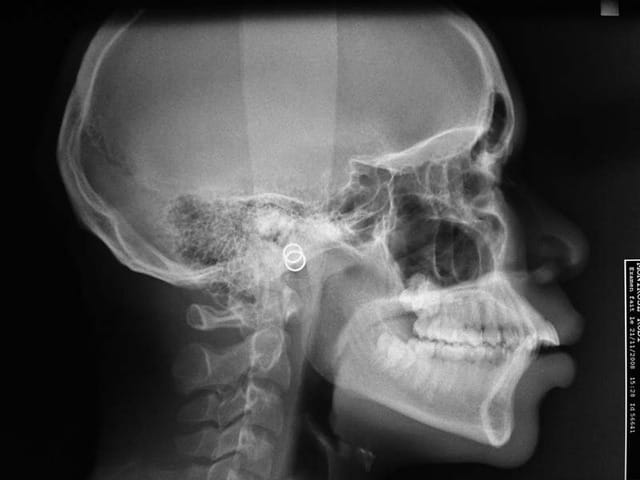

Bonjour, Bjc, est-ce que tu pourrais mettre la télé de profil s'il te plait?

1 p3qrc4 - Eugenol

Bjc.

18/07/2009 à 22h58

télé de profil

@+ Bjc.

Rx - Eugenol